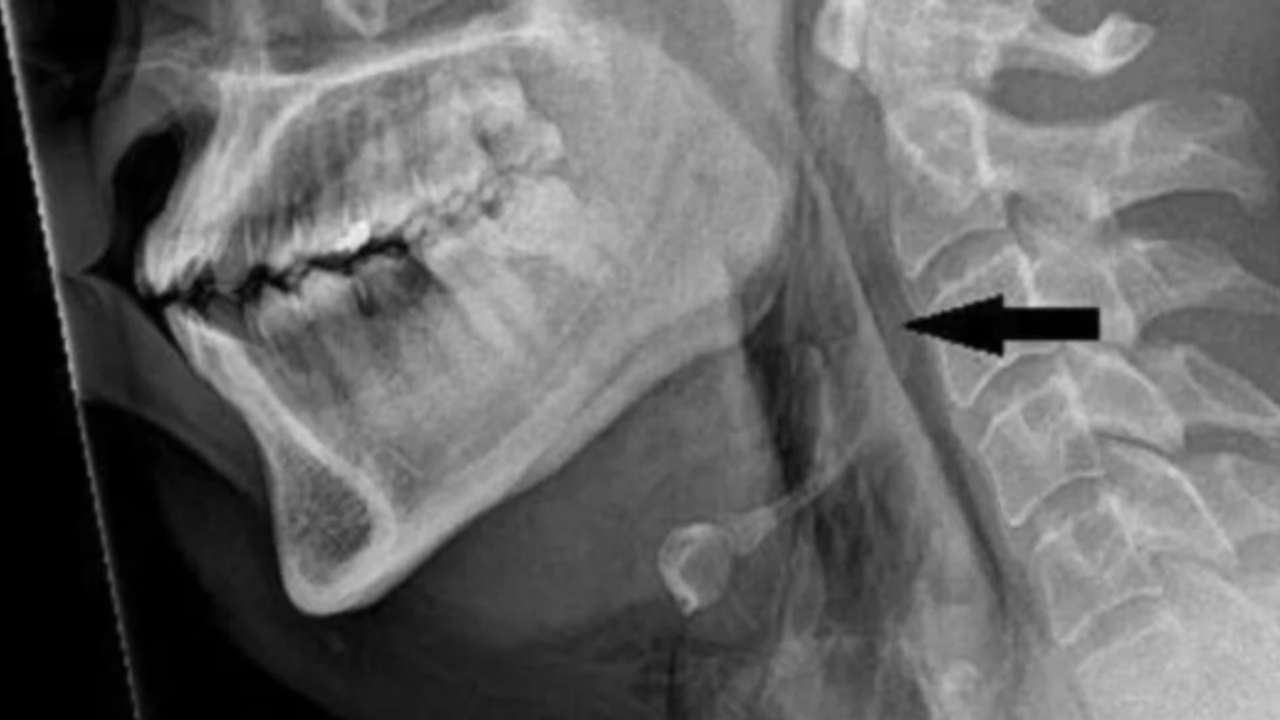

এই ঘটনার পর ওই ব্যক্তির গলার এক্স-রে করা হয়। সেখানেই আসল ঘটনা সামনে আসে। জানা যায় যে লোকটির অস্ত্রোপচারের এমফিসেমা ছিল, একটি রোগ যেখানে বাতাস ত্বকের গভীরতম টিস্যু স্তরের পিছনে আটকে যায়। পরবর্তীকালে, একটি সিটি স্ক্যানে দেখা যায় যে তার ঘাড়ের তৃতীয় এবং চতুর্থ কশেরুকার মধ্যে ছিদ্রটি অবস্থিত ছিল। তার ওপর তার ফুসফুস এবং তার বুকের মাঝখানে বাতাস জড়ো হয়েছিল। চিকিত্সকরা জানিয়েছেন যে "এই শারীরিক পরিস্থিতিতে নাক এবং মুখ বন্ধ করে হাঁচি আটকানোর ফলে শ্বাসনালীতে দ্রুত চাপ তৈরি হওয়ার কারণে" এই বড় শারীরিক ক্ষতি হয়েছিল।